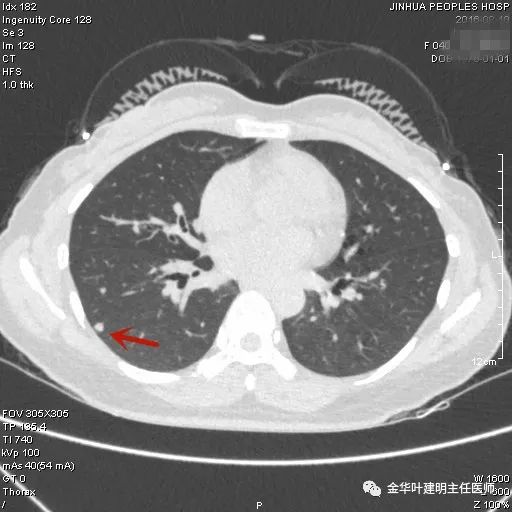

上图示结核。我们发现其有明显的卫星灶,如绿色箭头所示,主病灶处也是周边有模糊区域,病灶整体密度较为均匀(肿瘤容易生长不均致密度欠均匀,显杂乱)。